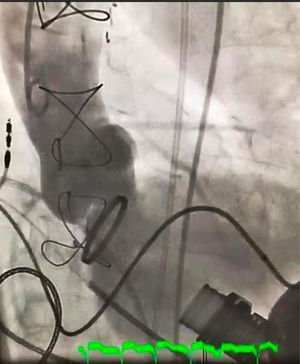

El implante fue un éxito, pasando de una IA severa (fig. 1) a una insuficiencia aórtica mínima (fig. 2) por aortografía y sin gradiente transvalvular.